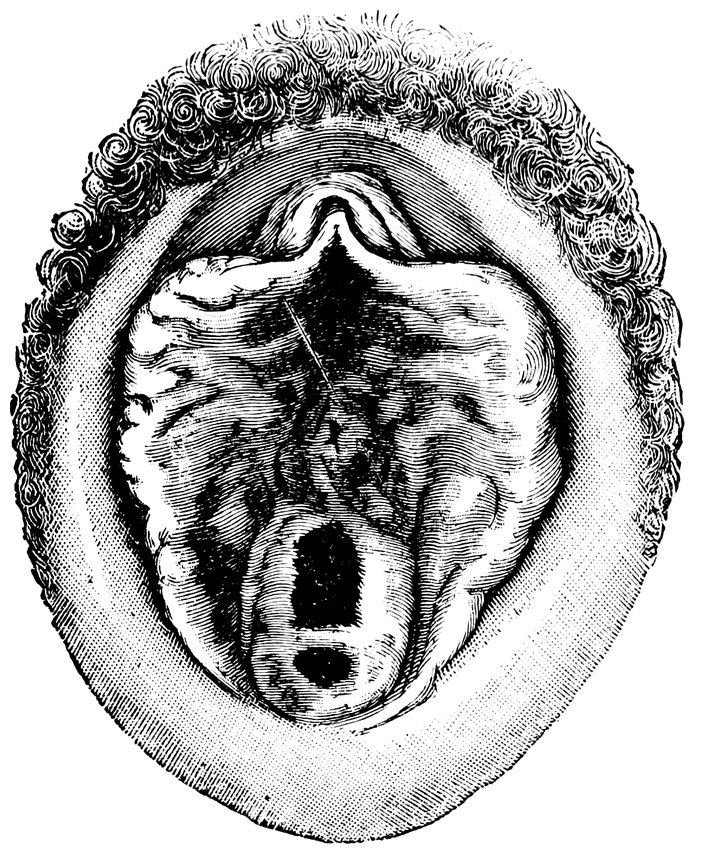

| 45. | Vaginal Inlet of a Multipara, without Carunculæ Myrtiformes. Slight Prolapse of Anterior and Posterior Vaginal Walls | 71 |

| 48. | The female pudendum, or vulva, with the labia majora | 204 |

| 49. | Vestibule of the vagina, with the labia minora or nymphæ, etc | 205 |